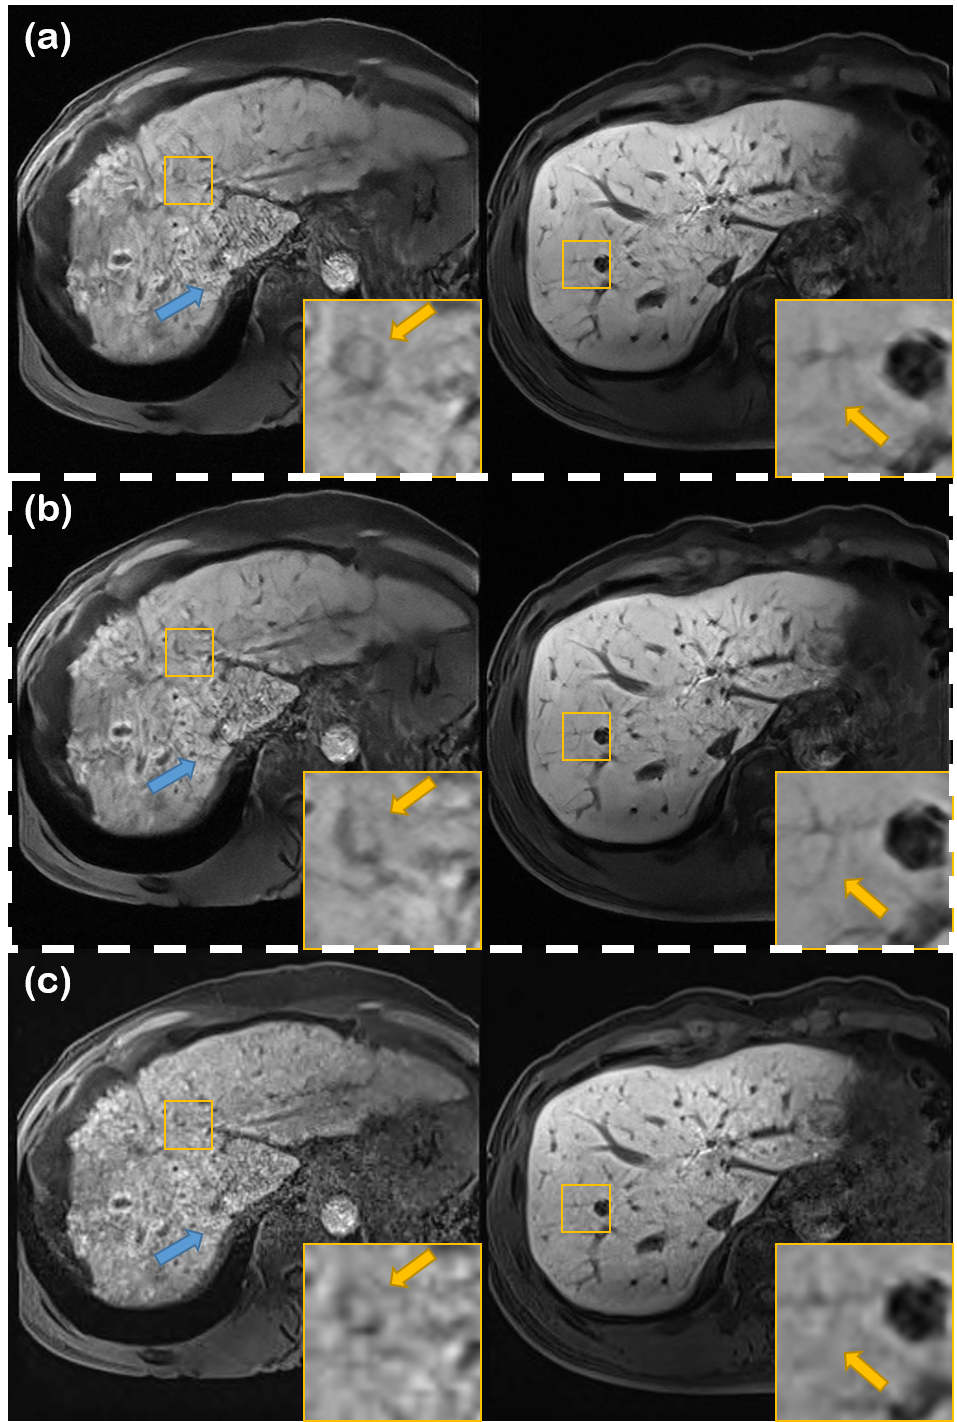

Refer to caption

Figure 3: Denoising results using various methods on different liver conditions. (a) N2N [13], (b) N2Score [15], (c) proposed method, and (d) input noisy image. Yellow boxes show results that are magnified. First row: early liver cirrhosis with hepatocellular carcinoma (HCC), second row: normal liver, third row: advanced liver cirrhosis.

Denoising results are summarized in Fig. 3, with the quantitative metrics in TABLE II. In Fig. 3, we see that our method is the only method to effectively remove the noise while sharpening the image, regardless of the given condition of the liver. This is also consistent with the metrics given in TABLE II, where our method is the highest scoring method both in terms of SNR and CNR. Notably, it can be seen from TABLE II that while all methods have higher SNR than the input such that it is statistically relevant, R2D2+ is the only method which does not compromise CNR. This can be deciphered in two aspects - 1) R2D2+ is the only method that explicitly enhances the resolution with the same network that was used to denoise the image. 2) Posterior sampling does not produce blurry output, as opposed to MMSE estimates.

From TABLE II, we do observe that self-supervised learning based methods (i.e., N2N, N2Score) have much better performance than BM3D. Nevertheless, the metrics lack far behind R2D2+, especially in terms of CNR. This can also be visually inspected in Fig. 3 (b-d). While we can see relatively clearly that denoising has taken place as opposed to the noisy input, the denoised output tend to be washed out, with unclear boundaries and vessel structures. We note that Nei2Nei performs even worse than BM3D, which we conjecture to be stemming from its poor generalization capability. For further experimental results with detailed information about the statistical analysis, together with more figures including comparisons with BM3D, see Fig. 7.

In Fig. 7, we show additional experimental results, comparing extensively with block-matching 3D filtering (BM3D) [47], Noise2Noise (N2N) [13], and Noise2Score (N2Score) [15]. It is clear from Fig. 7 (d) that the proposed method clearly outperforms all methods, by reconstructing sharp vessel structures, while removing excessive noise around such structure. All other comparison methods fall heavily behind the proposed method, especially in terms of preserving high-frequency detail.